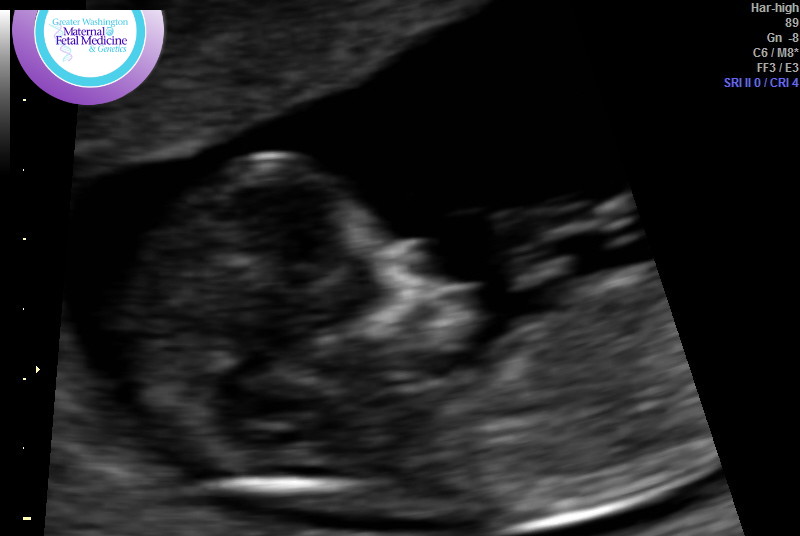

Here are the nub/skull pics again:

Attachment 41115Attachment 41116Attachment 41117Attachment 41118Attachment 41119